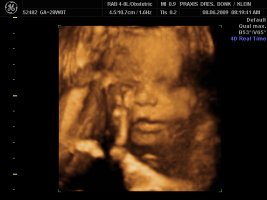

Und dann haben wir endlich unser Video gemacht, Zeit hatten wir ja nun genug und das ist voll süß geworden, sie war wohl auch wie Mama müde, denn sie hatte öfter mal gegähnt und mit den Augen geblinzelt :love1 ...kann es kaum noch erwarten die Kleine in die Arme zu nehmen :applaus

Und wir haben endlich ein Beweisfoto bekommen, dass es ein Mädchen ist...

Hier ein paar Bilder von Montag, neben dem Video haben wir auch sehr viele Bilder mitbekommen.... :love1

Anhänge

• Bild 1.jpg

Bild 1.jpg

72,4 KB · Aufrufe: 72

• Bild2.jpg

Bild2.jpg

75,1 KB · Aufrufe: 72

• Bild3.jpg

Bild3.jpg

61,5 KB · Aufrufe: 72

@Imke ui was für schöne Bilder, will auch! *jammer*